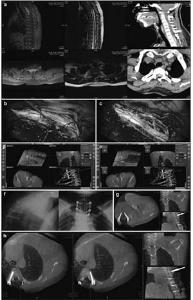

20171023161042 Figure 1 Preoperative, intraoperative, and postoperative images of patients with atlantoaxial dislocation and occipitocervical fusion. Preoperative cervical radiography in the side (a), anteflexion (b), and supine (c) positions reveals odontoid instability and a backward and upward shift. Preoperative computed tomography (CT) (d) and magnetic resonance imaging (MRI) (e) show that the backward and upward dislocation of the C2 odontoid impacts the brain stem. The foramen magnum is narrow, and the cervical cord void is visible. (f) Implantation direction and C2 angle. Pars screws are planed under intraoperative navigation. (g) O-arm three-dimensional scan, after screw implantation, shows that the Pars screw to the right of C2 penetrates the bone cortex and is near the vertebral artery. Lateral radiography (h), sagittal CT (i), and a T2 sagittal scan (j), 1 week after the operation, show firm screw fixation in a good position and inferoanterior displacement of the odontoid to the C1 level, essentially achieving normal anatomical reduction. Brain stem compression is released, and the posterior cranial fossa is fully decompressed.